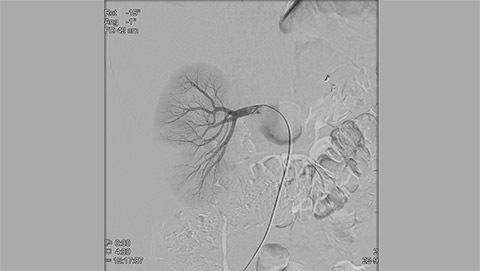

XperCT extends the capabilities of the interventional suite offering CT like imaging to visualize bone, soft tissue and vessels in case of contrast enhanced acquisition. XperCT supports fast abdominal protocols with 5 to 8 seconds acquisition time for excellent image quality while significantly minimizing respiratory artifacts. The XperCT 3D volume is displayed automatically within 8 to 15 seconds after the acquisition and confirms selective targeting of hepatic lesion and helps avoid untargeted embolization and drug delivery.